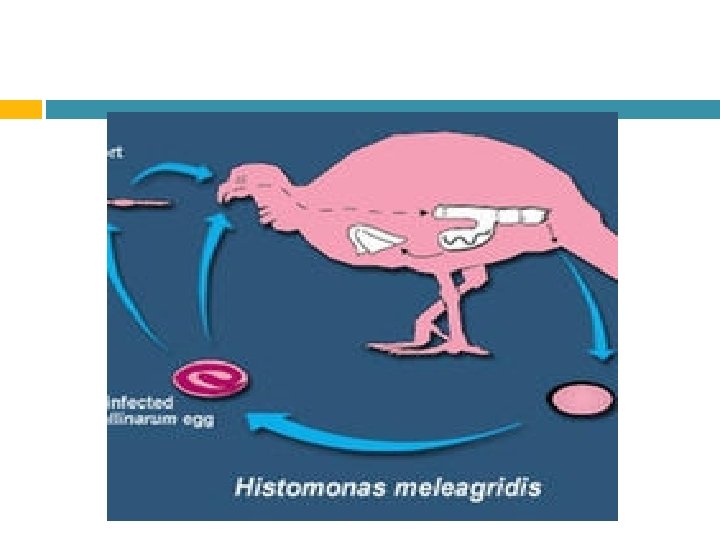

Etiología Histomona meleagridis

Epidemiología Se caracteriza por su gran capacidad, para infectar o parasitar órganos como el ciego y el hígado Es de relevancia destacar que la enfermedad en el caso de los pavos, presenta una alta tasa de mortalidad en aves jóvenes (60 -90%)

Tratamiento No existe y está orientado a la prevención mediante la desparasitación con bencimidazoles para destruir al hospedador intermediario (Heterakis).

Prevención y Control Controlar la presencia del nematodo Heterakis gallinarum No criar aves de diferentes especies en las mismas instalaciones. No criar aves jóvenes junto con las adultas. Criar a las aves en altura para evitar el consumo de alimento directamente de la tierra (lombriz). Seguimiento de gusanos de tierra en las instalaciones. Evitar humedad en camas y pisos.